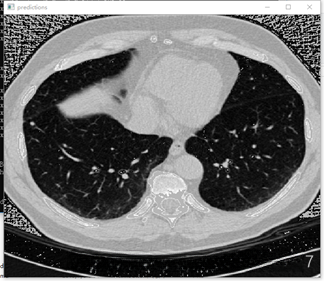

训练了大概3天,迭代了48000次,loss值约0.03(GTX1080)。

原图:

预测:

在应用yolov3算法进行肺结节检测时,发现其在实际应用中仍存在一定局限性。具体表现为:1)迭代训练不足导致模型尚未达到充分收敛的状态;2)有必要对训练数据集进行聚类分析以优化参数设置,并调整anchor框大小与比例参数设置以进一步提升检测精度。